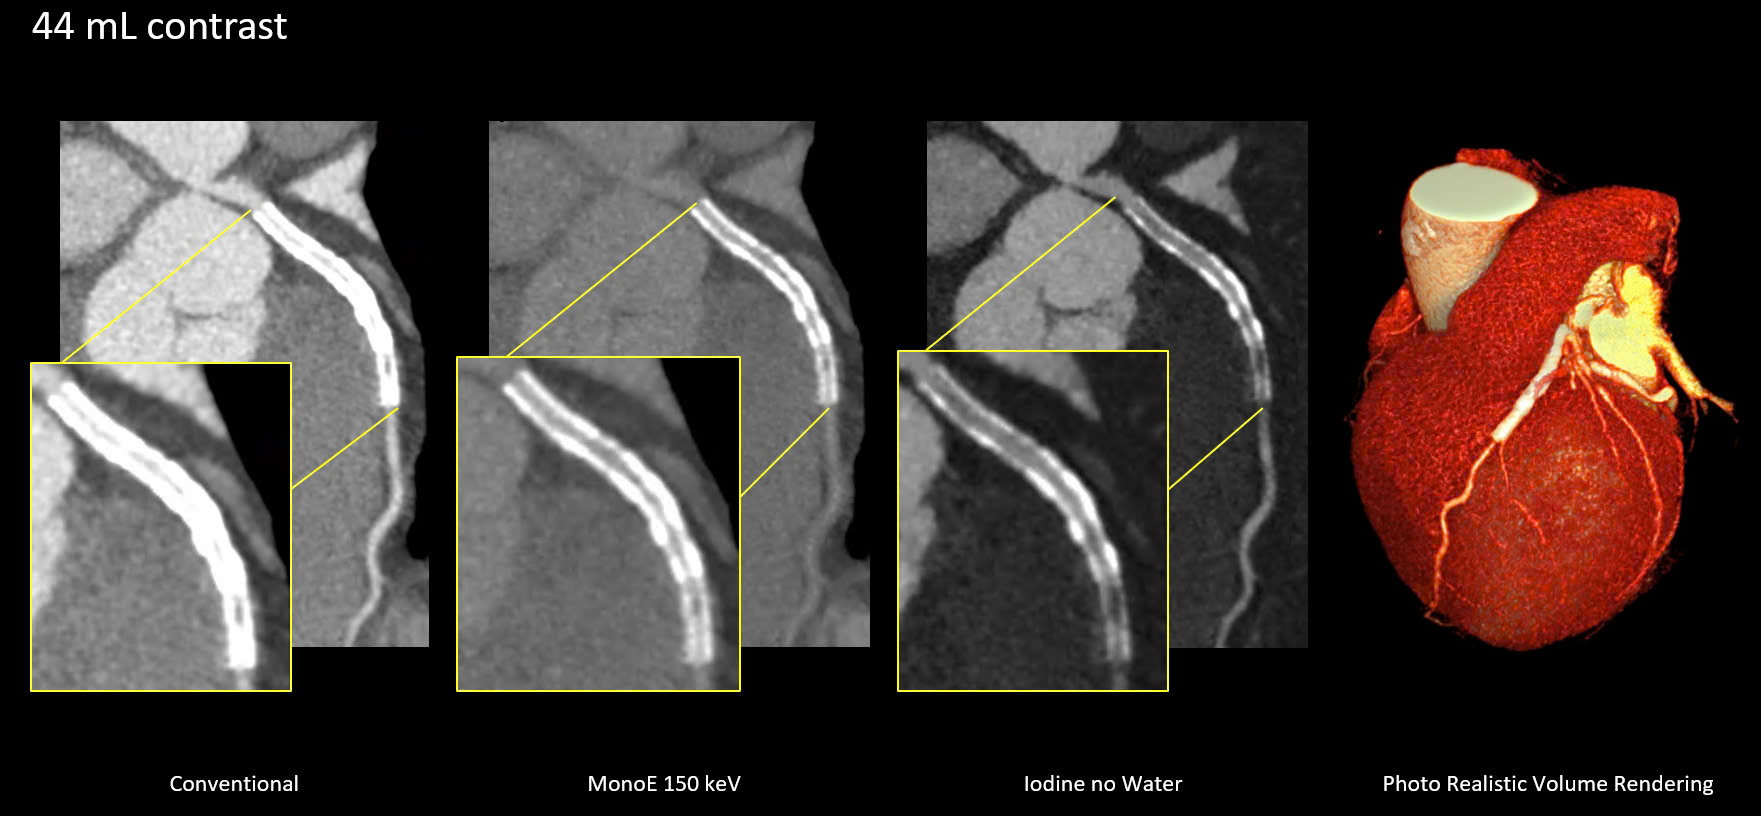

Bệnh nhân được chỉ định thay van động mạch chủ qua da. Các bác sĩ đã sử dụng chương trình TAVI planning trên hệ thống Spectral CT7500 với liều lượng thuốc cản quang giảm, nhờ tính năng phổ MonoE cho phép đảm bảo hình ảnh có độ tương phản cao dù bệnh nhân có nền bệnh phức tạp.

Đối với bệnh nhân cần chụp mạch vành, hệ thống cho phép đánh giá đồng thời tình trạng mạch vành và khả năng sống còn của cơ tim trong một lần chụp.

Nhờ ứng dụng AI và công nghệ phổ, hình ảnh tim được ghi lại rõ nét, loại bỏ chuyển động tim với liều tia thấp, hỗ trợ chẩn đoán chính xác mà không cần can thiệp xâm lấn – từ đó tiết kiệm chi phí cho người bệnh.